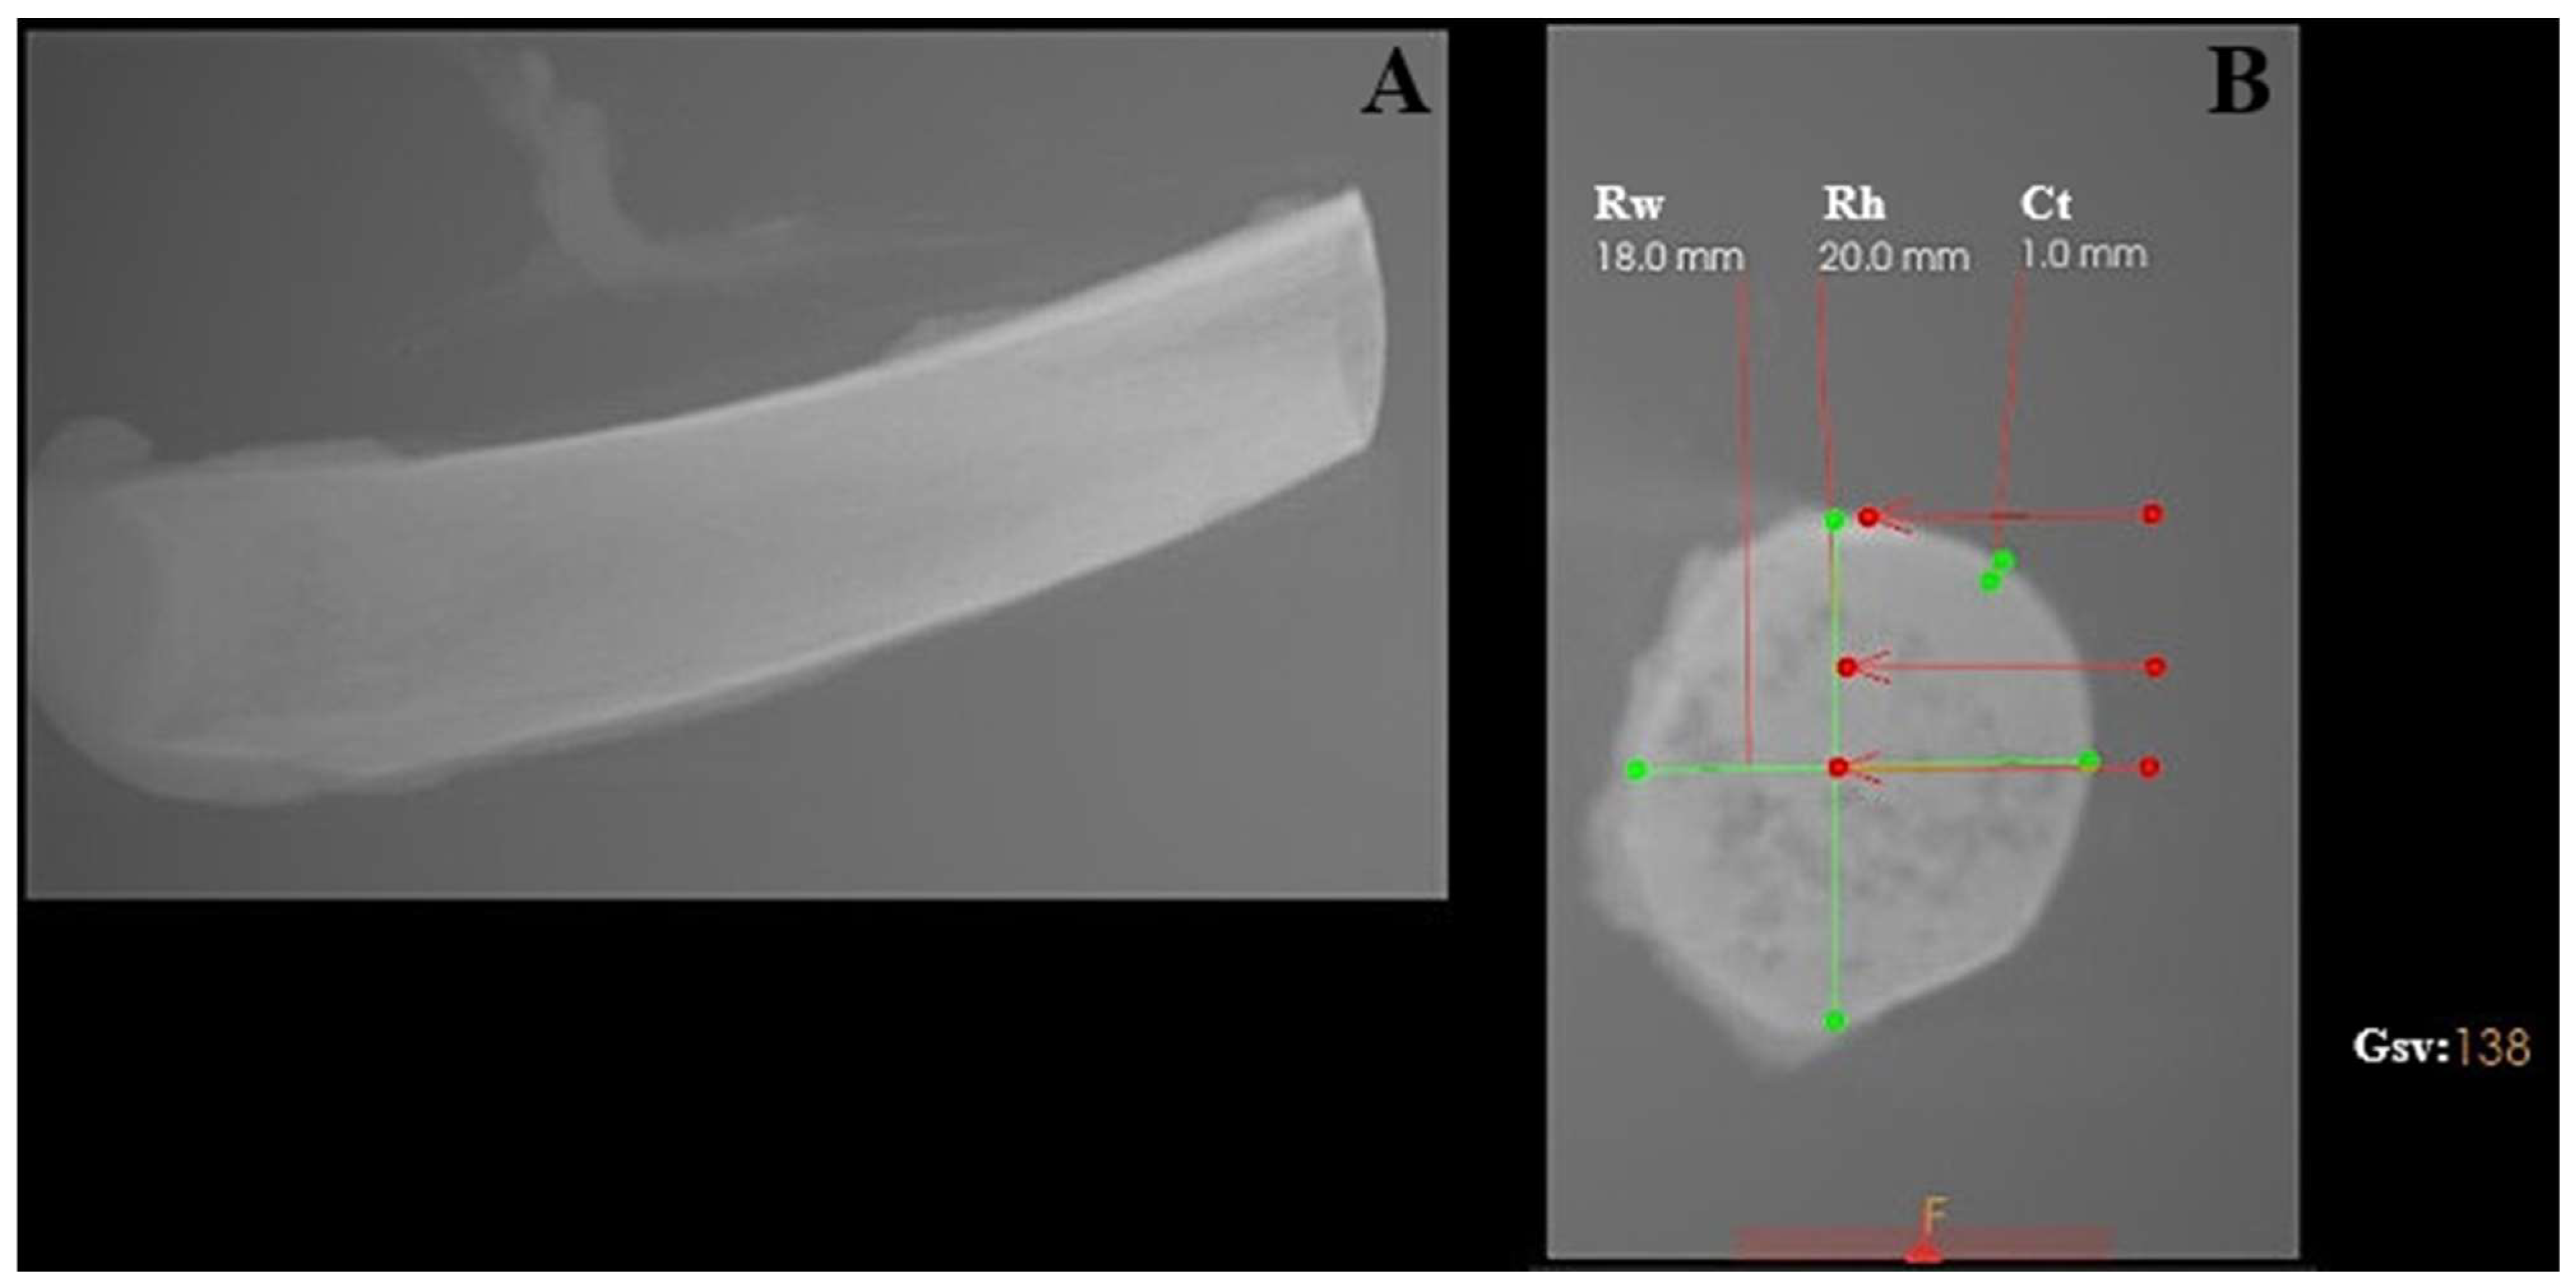

The experimental model consisted of porcine rib bones (Złotnicka Biała breed) of comparable size with respect to length, thickness, and width. The mean diameter of the ribs used in this study was 18.23 ± 2.35 mm, while the average thickness of the cortical bone layer was 1.6 ± 0.7 mm.

Bone density was assessed at different depths along the osteotomy site, reflecting the anatomical heterogeneity of the rib structure. In the cortical region, bone density measured in grayscale values corresponded to a range of approximately 700–1100 HU. At a depth of 5 mm, density values decreased to approximately 150–300 HU, while at 10 mm depth, values ranged between 50 and 150 HU, indicating predominantly trabecular bone structure (see Figure 1).

Figure 1.

Characterization of the porcine rib used as the experimental bone model, analyzed using CS 3D Imaging software (version 3.10.48; Carestream Dental, Atlanta, GA, USA). (A) Longitudinal view of the porcine rib. (B) Cross-sectional view showing geometric measurements and grayscale-based bone density evaluation. Rw—rib width; Rh—rib height; Ct—cortical thickness; Gsv—grayscale value measured in the ventral part of the rib.

The porcine rib model was selected due to its combined cortical–cancellous architecture and is commonly regarded in implantology research as resembling medium-density human jawbone (D2–D3) rather than very dense cortical bone (D1) or highly trabecular bone (D4) [25].